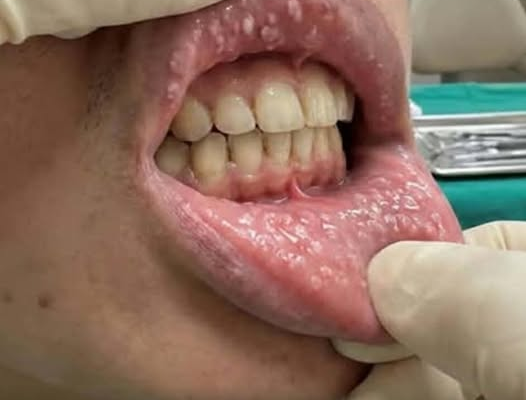

1. Fordyce Glands

One of the most common benign causes of bumps on the lips is Fordyce glands. These are tiny sebaceous (oil) glands that naturally occur on the lips and other mucosal areas. Unlike typical sebaceous glands associated with hair follicles, Fordyce glands appear on hairless regions of the lips and are entirely normal.

- Appearance: Small, white or yellowish spots

- Symptoms: Usually painless and non-inflamed

- Treatment: None required; harmless

Fordyce glands are not contagious and do not pose any health risk. They can be more visible in adults with lighter skin, and while they may cause cosmetic concerns for some, they generally remain stable throughout life.